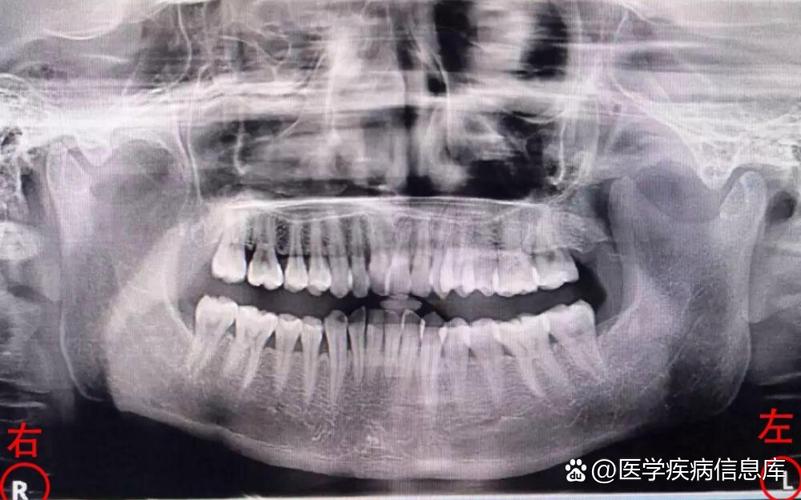

- 权衡利弊:牙医开具全景片检查,是为了获得诊断疾病和制定治疗计划所必需的全面信息,其带来的诊断价值远远大于其微乎其微的辐射风险,没有这些影像,可能会漏掉重要的疾病(如埋伏牙、囊肿、肿瘤、严重的牙槽骨吸收等),导致更严重的后果。

- 儿童:儿童对辐射比成人更敏感,但儿童在正畸、拔除多生牙等治疗中,全景片又是必不可少的,牙科医生会遵循“ALARA”(As Low As Reasonably Achievable,合理可行尽量低)原则,使用儿童专属的更低剂量参数,并严格遮盖甲状腺等敏感部位。